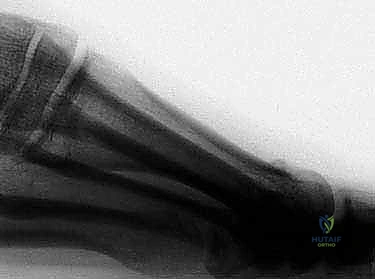

يتم إجراء القطع العظمي بشكل مائل، بدءاً من السطح الأخمصي القريب (Plantar-proximal) إلى السطح الظهري البعيد (Dorsal-distal). هذا الاتجاه المائل للقطع يوفر استقراراً ميكانيكياً هائلاً ضد قوى الإزاحة التي تحدث أثناء تحمل الوزن والمشي.

الخطوة الثالثة: إجراء القطع العظمي (The Mau Cut)

باستخدام منشار جراحي دقيق جداً (Micro-saw)، يقوم الجراح بعمل القطع المائل المميز لتقنية ماو. يتطلب هذا الأمر دقة هندسية وخبرة طويلة لضمان الزاوية الصحيحة للقطع.